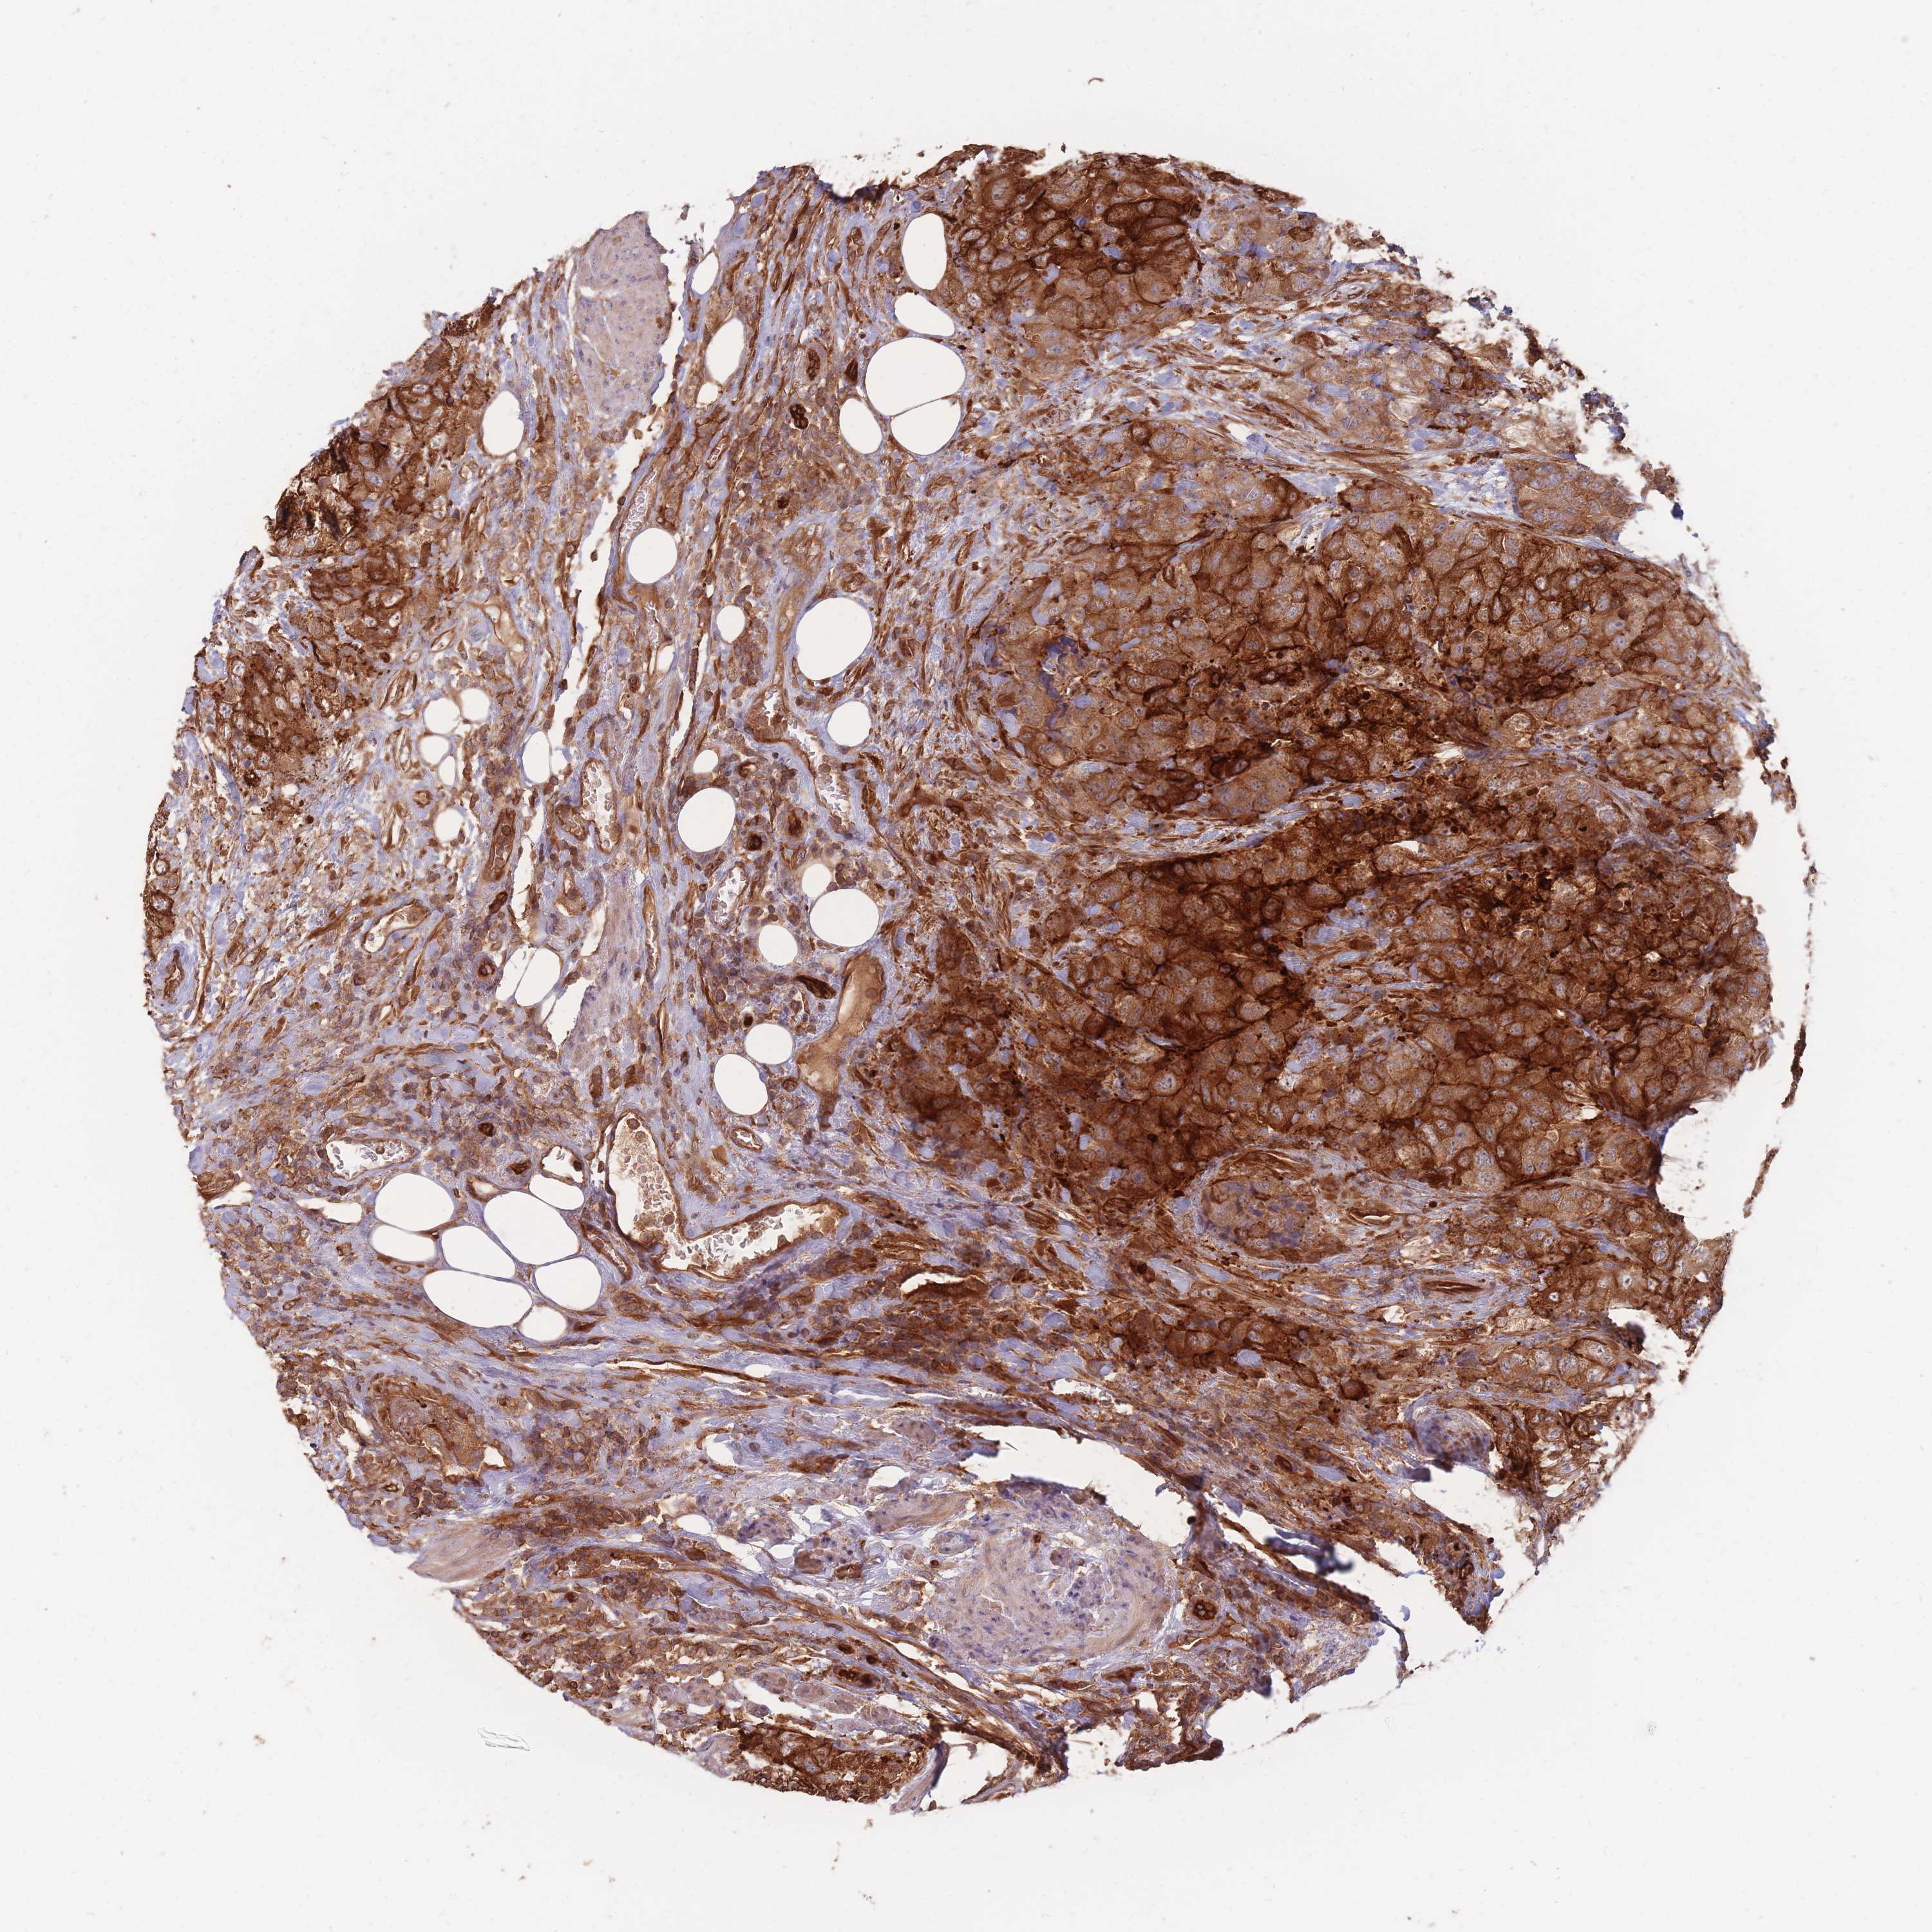

UROTHELIAL CANCER - Protein expressioni

A mouse-over function shows sample information and annotation data. Click on an image to view it in a full screen mode. Samples can be filtered based on level of antibody staining by selecting one or several of the following categories: high, medium, low and not detected. The assay and annotation is described here.

Note that samples used for immunohistochemistry by the Human Protein Atlas do not correspond to samples in the TCGA dataset.

Antibody stainingi

Antibody staining in the annotated cell types in the current human tissue is reported as not detected, low, medium, or high, based on conventional immunohistochemistry profiling in selected tissues. This score is based on the combination of the staining intensity and fraction of stained cells.

Each image is clickable and will lead to virtual microscopy that enables deeper exploration of all samples and also displays staining intensity scores, fraction scores and subcellular localization as well as patient and tissue information for each sample.

Antibody HPA020433

Staining

High

Medium

Low

Not detected

Intensity

Strong

Moderate

Weak

Negative

Quantity

>75%

75%-25%

<25%

None

Location

Nuclear

Cytoplasmic/membranous

Cytoplasmic/membranous,nuclear

Urothelial carcinoma, High grade

Urothelial carcinoma, NOS

Urothelial carcinoma, Low grade